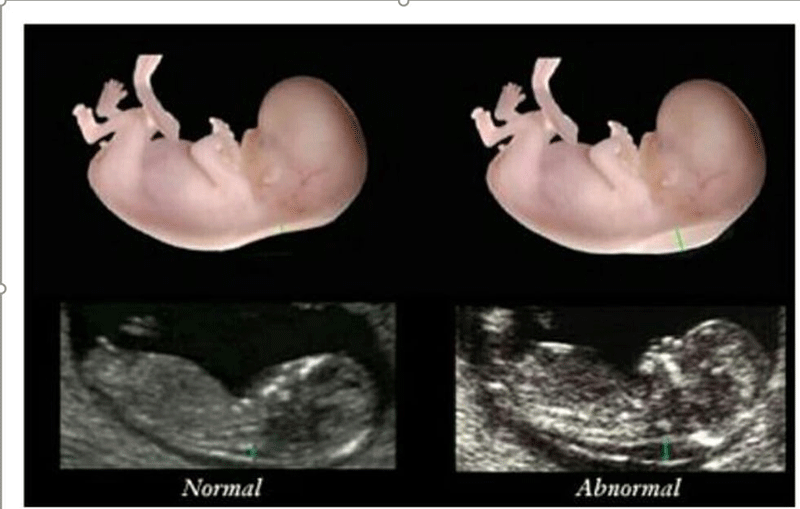

nt是胎儿颈后透明袋的简称,全称为(nuchal teanslucency),nt检查就是胎儿颈后透明带检查,检查胎儿颈后部皮下组织内液体积聚的厚度。

nt检查的主要作用就是获得nt值,通过nt值诊断胎儿是否正常,是否有染色体疾病和其他原因造成胎儿畸形,如果通过nt值提示胎儿有异常,在做四维彩超和唐氏筛查的时候将会重点关注。

nt检查正常值一般是在≤2.5mm,只要通过nt检查发现nt值在正常值范围内,就可不用担心了,nt检查属于一次检查。

nt值异常原因

1、通过nt检查,nt值增厚的原因可能是因为测量错误、测量误差等原因造成;

2、如果没有测量误差,就是真正病理上的问题,就是胎儿染色体异常、胎儿大动脉畸形、胎儿静脉导管血流异常或者是淋巴系统排泄失常等原因,